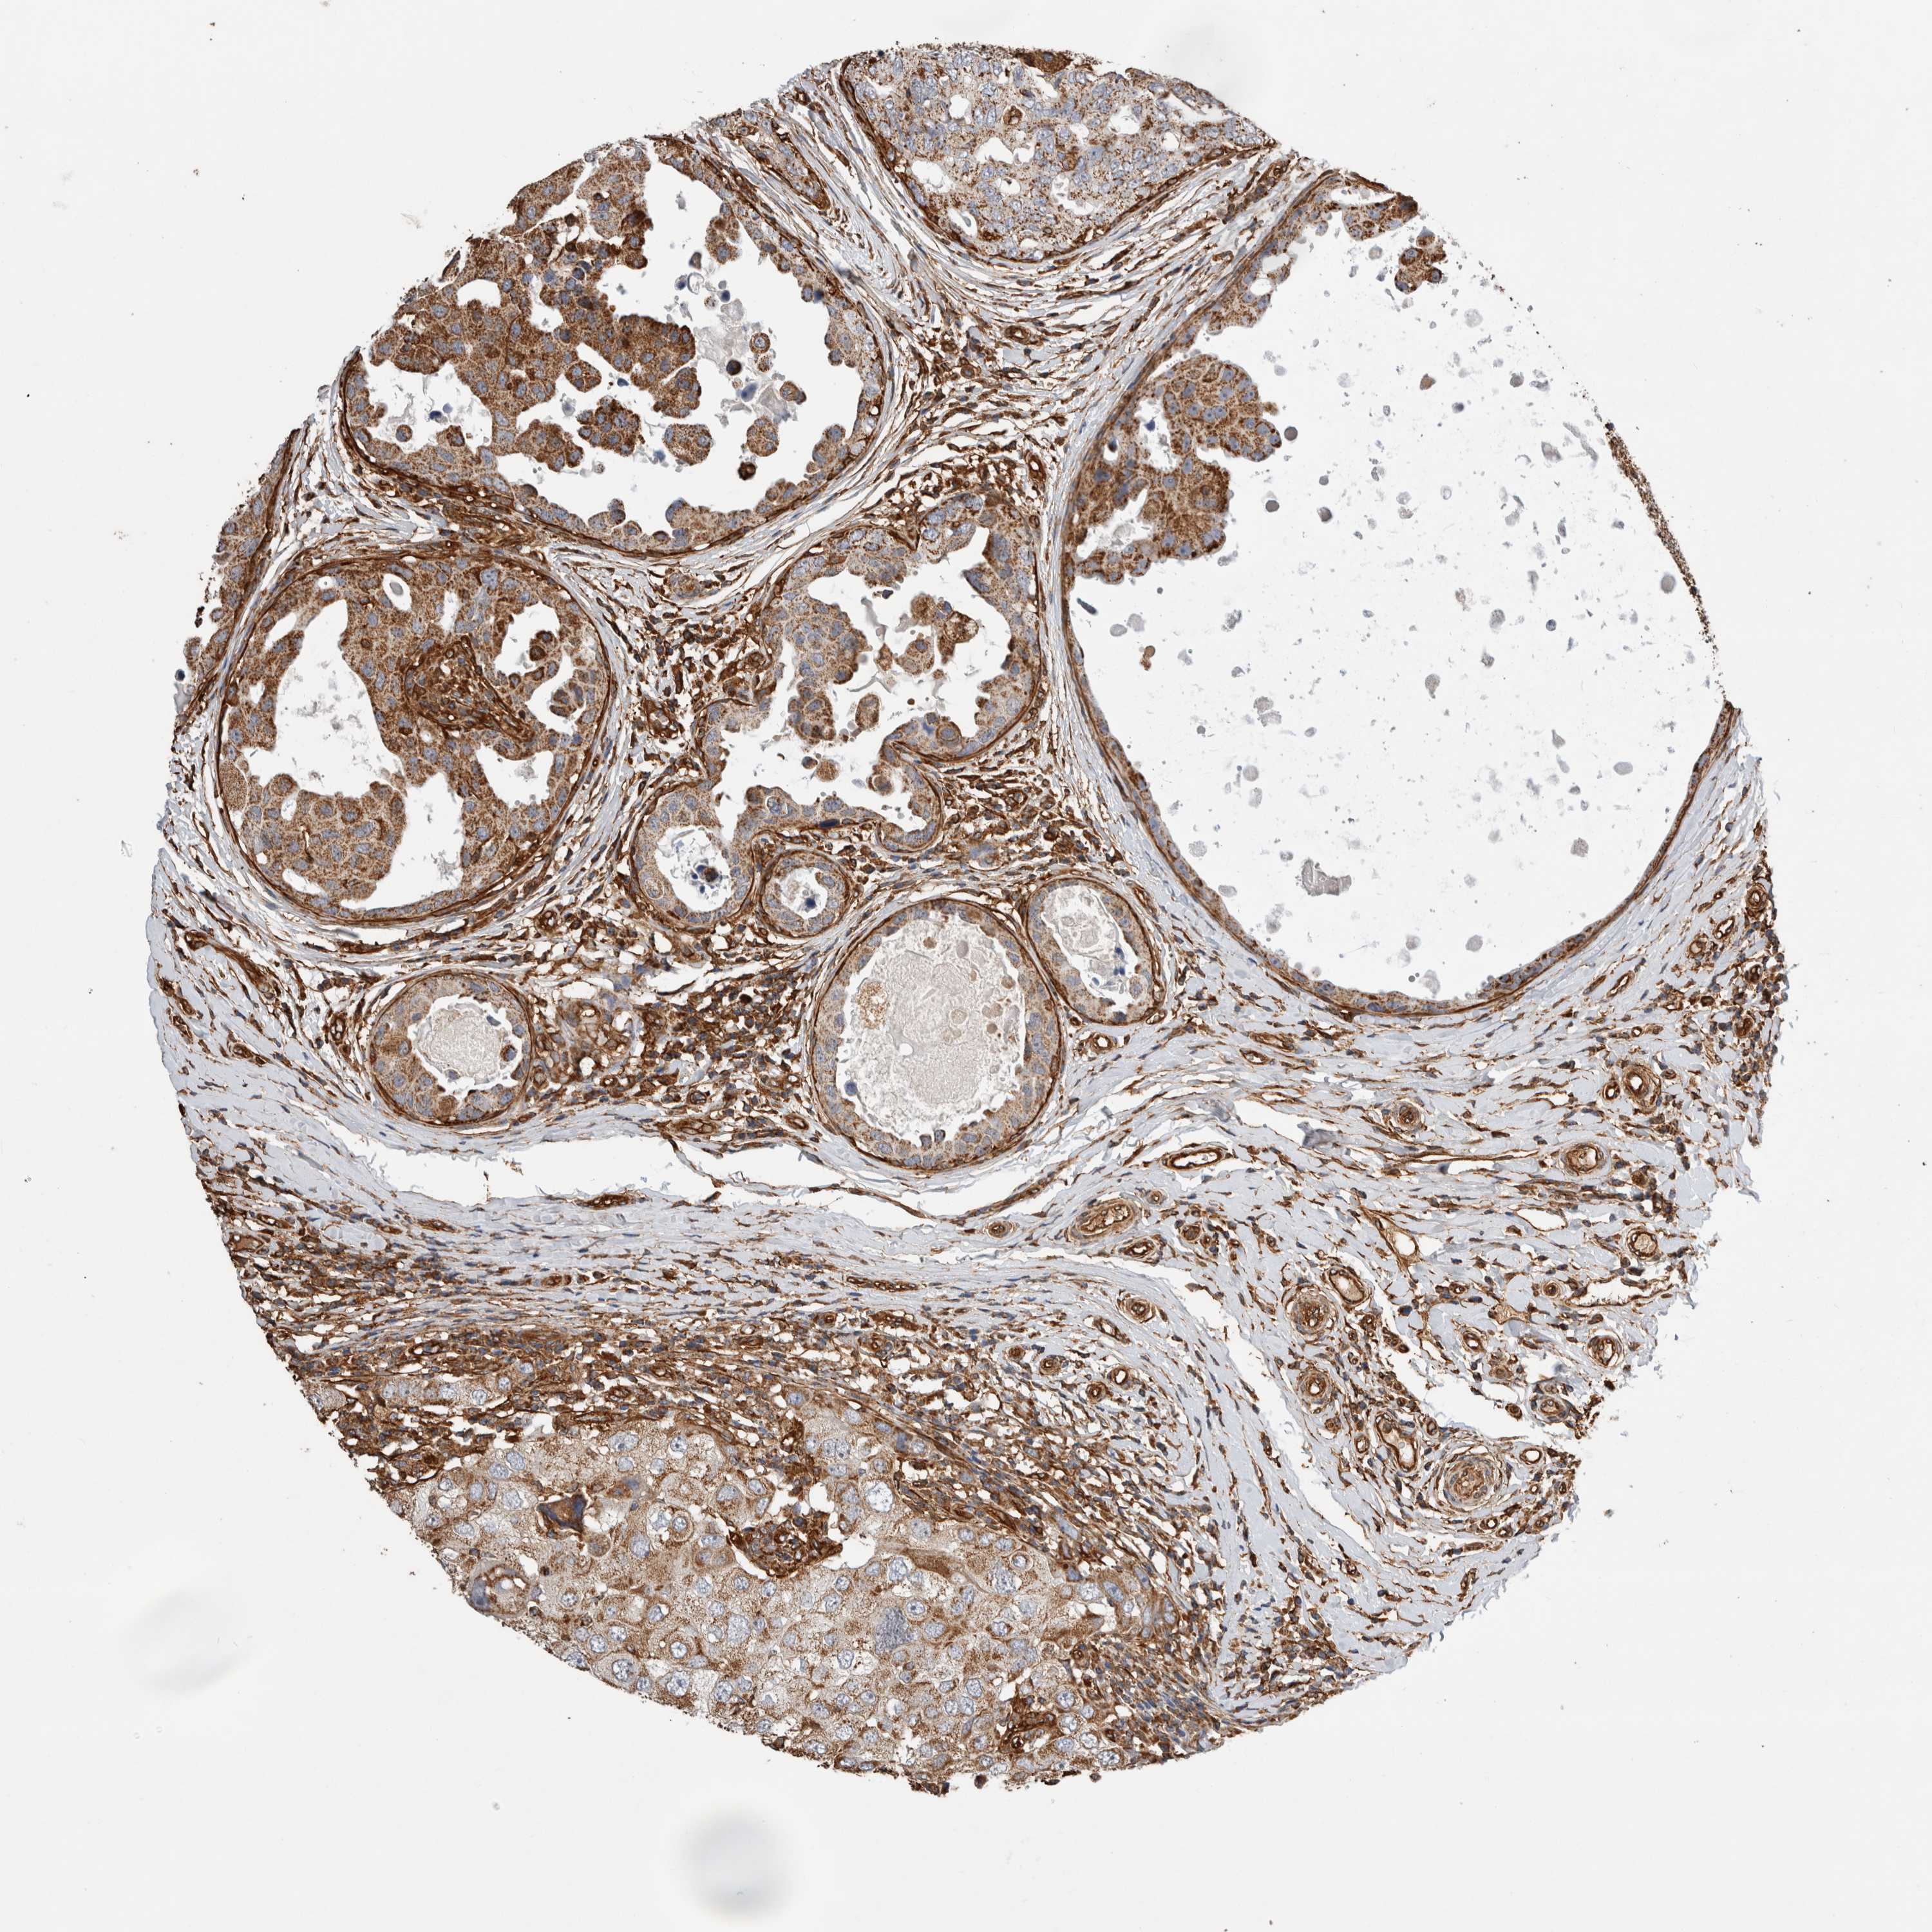

CANCER BREAST CANCER Show tissue menu

BRCA TCGA BRCA VALIDATION PROTEIN EXPRESSION

Breast cancer

Human cancer